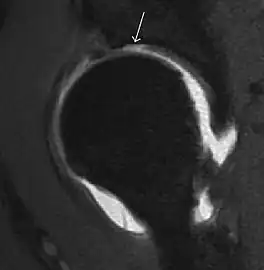

Synovial chondromatosis can be confidently diagnosed by X-ray when calcified cartilaginous chondromas are seen. However, other synovial proliferative processes, such as pigmented villonodular synovitis, require MRI for accurate diagnosis, although noncalcified synovitis can be suspected in radiographs by indirect signs, such as soft tissue swelling and/or erosions in the femoral head, femoral neck, or acetabulum (Figure 7).[1]

Figure 7:

-

Axial CT image of pigmented villonodular synovitis eroding the posterior cortex of the femoral neck.[1] -

Sagittal T2* gradient echo image showing a posterior soft tissue mass with hypointense areas secondary to hemosiderin deposition.[1] -

X-ray of synovial chondromatosis.[1] -

CT of synovial chondromatosis.[1]

In synovial proliferative disorders, MRI demonstrates synovial hypertrophy. In the case of PVNS, characteristic foci of low signal intensity related to hemosiderin deposition are better seen on gradient echo T2* images (Figure 7). In the case of synovial osteochondromatosis, the synovial hypertrophy is accompanied by intermediate signal cartilaginous loose bodies and/or low signal calcified loose bodies.[1]